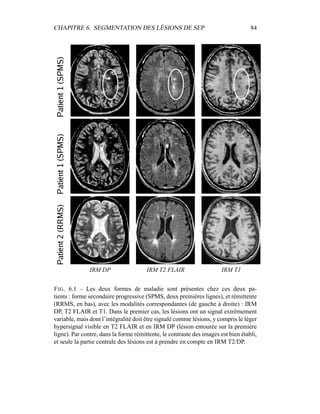

c’est donc sur elle que portera l’analyse lors de la segmentation en tissus et de la

présentation du modèle de volume partiel. Les autres modalités seront utilisées a

posteriori.

4.4 Segmentation en tissus.

4.4.1 Algorithme

Le but de cette segmentation en tissus sains est leur caractérisation, afin de

pouvoir construire un premier processus de détection des lésions de SEP. Même

si les 4 séquences (T2 FSE / DP, T1, T2 FLAIR) sont disponibles, la segmenta-

tion ne sera menée dans un premier temps que sur le couple T2/DP, alors que les

autres séquences – T1, T2 FLAIR – montreront tout leur intérêt pour la détection

des lésions et leur spécification : ceci permet de n’effectuer la segmentation que

sur des images vierges de tout rééchantillonnage. En outre, nous ferons délibéré-

ment l’impasse sur certains processus décrits dans la littérature pour améliorer la

qualité visuelle de la segmentation – les contraintes sur le voisinage, par exemple

– puisque notre but est d’obtenir un critère sur l’intensité qui sera raffiné ensuite

par contraintes spatiales.

Dans sa formulation la plus simple, le processus de segmentation prend un

ensemble multi-séquences à segmenter – les deux images T2 / densité de pro-

tons, auxquelles le masque binaire du cerveau a été appliqué – et fournit en sortie

3 labélisations : matière blanche, matière grise, LCR. Comme indiqué dans les

CHAPITRE 4. SEGMENTATION EN TISSUS 53

équations 4.10 et 4.11, l’algorithme EM donne deux grands résultats :

– la labélisation des segmentations via les γk

i

– l’estimation des paramètres du modèle µk et Σk.

4.4.2 Présentation des résultats

Pour éliminer dans un premier temps l’influence des lésions de SEP, un témoin

a été choisi pour cet exemple, et les résultats sont présentés dans la figure 4.5. Pour

la segmentation du masque du cerveau, seule la segmentation était intéressante.

Une mauvaise estimation des paramètres de classes, ou un mauvais modèle était

sans importance tant que la segmentation était valide. Par contre, dans le cas de la

segmentation en tissus, avoir une bonne estimation des paramètres est primordial,

car c’est à partir de là que les lésions de SEP vont être segmentées. Pour obser-

ver la qualité de la segmentation dans la figure 4.5, il faut donc en permanence

regarder deux espaces reliés.

– L’espace des intensités : visualisé via l’histogramme conjoint entre les deux

modalités, il est représenté par les paramètres de classes µk et Σk. Une mé-

thode pour visualiser ces paramètres est de tracer l’estimateur de confiance

donné par p(Z = z) = cte. Dans un espace 2D, cet estimateur est en fait

l’ellipse de Mahalanobis donné par 1

2

(X − µk)T

Σ−1

k (X − µk) = λ. Dans

toutes les figures similaires à la figure 4.5, les ellipses vérifieront λ = 1.

Pour avoir une meilleur visibilité de l’histogramme, celui-ci est en fait un

log-histogramme : la couleur de chaque pixel de l’image correspond au log

du nombre d’occurences du couple (IT2, IDP ) correspondant dans le couple

d’image IRM T2 / IRM DP. Ceci permet essentiellement de visualiser sur

le même histogramme le LCR avec le reste des tissus, bien que le nombre

de voxels correspondant au LCR soit très faible.

– L’espace des images, dans lequel les segmentations sont effectivement vi-